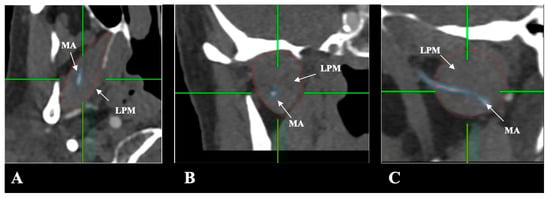

- Lateral (superficial) to the LPM: Detected in 321 sides (64.2%). This configuration was consistently visualized in axial, coronal, and sagittal planes (Figure 2).

- Medial (deep) to the LPM: Identified in 148 sides (29.6%), best appreciated on axial and coronal reconstructions (Figure 3).

- Intramuscular (transversing the LPM fibers): Found in 31 sides (6.2%), clearly depicted in all planes (Figure 4).